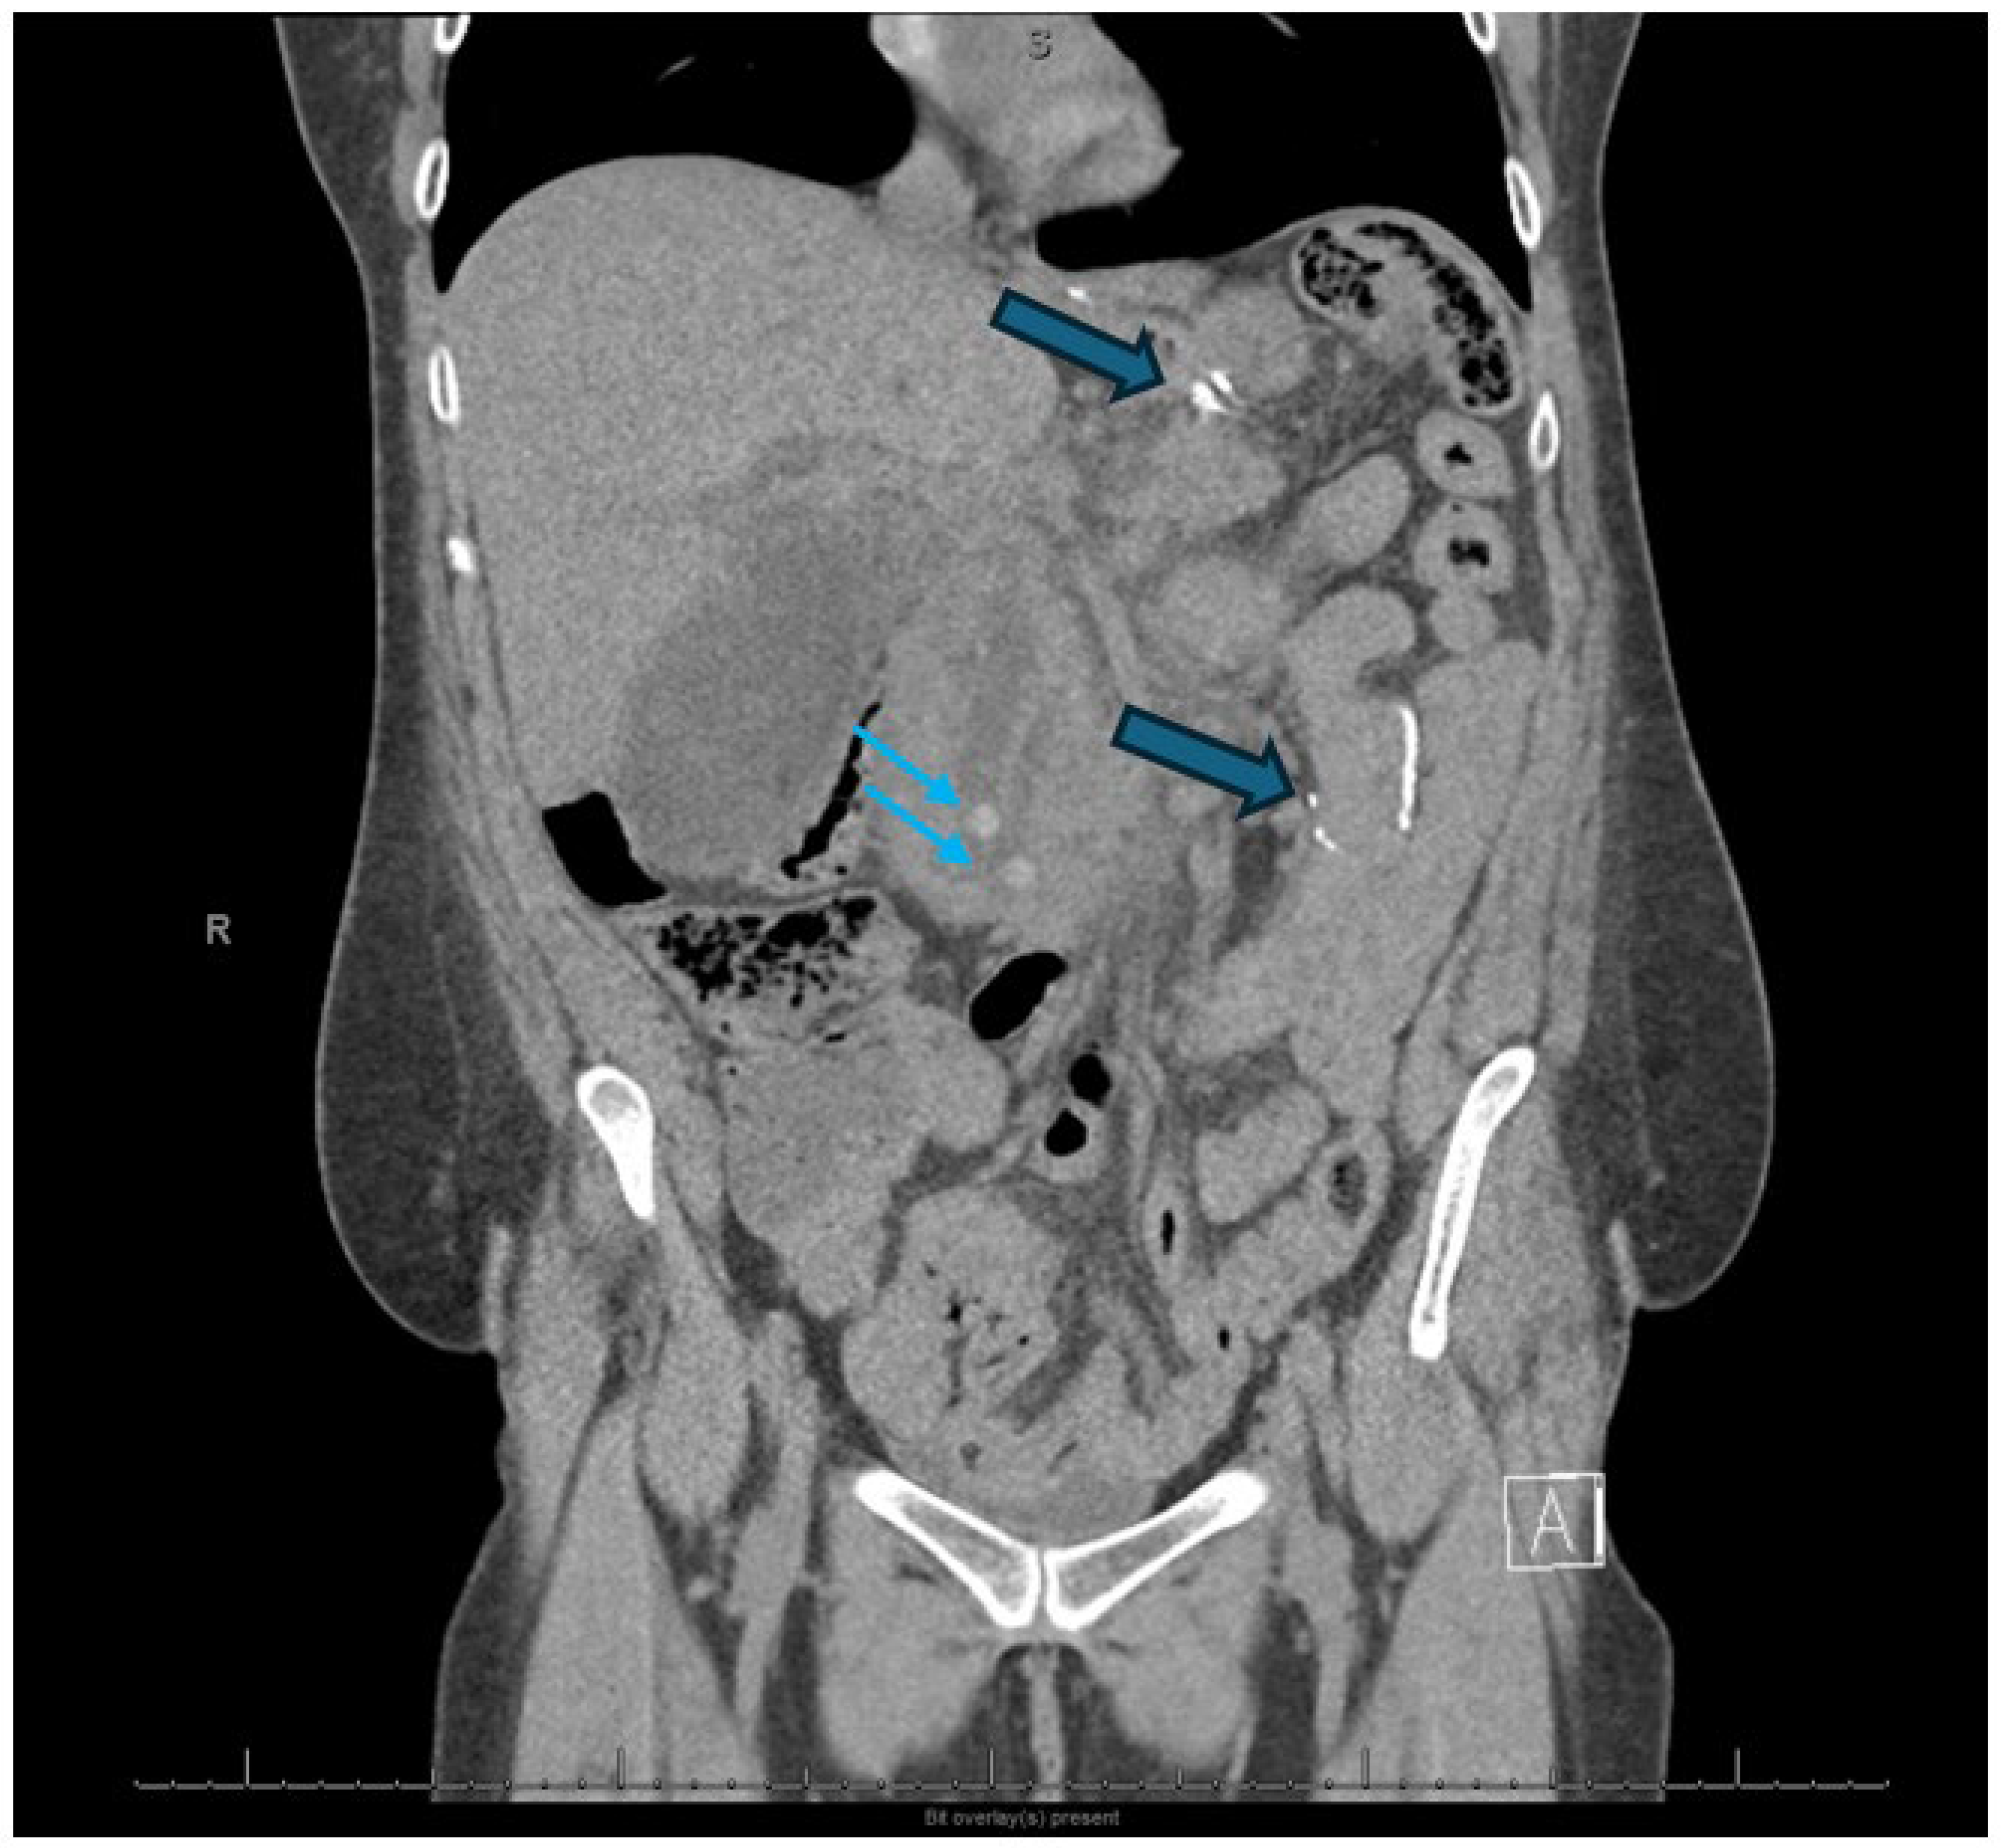

2.3. Infected Pancreatic Necrosis

2.4. Endoscopic Ultrasound-Guided Techniques for Walled-Off Pancreatic Necrosis (WON)